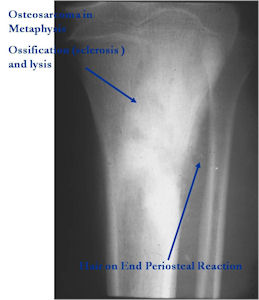

Aggressive Osteoblastoma vs. Osteosarcoma

Osteosarcoma:

- Cellular atypia

- High mitotic rate

- Atypical mitotic figures

- Abundant lacelike osteoid

- Permeative growth into adjacent bone and soft tissue

- Presence of neoplastic cartilage

- No peripheral shell of reactive bone